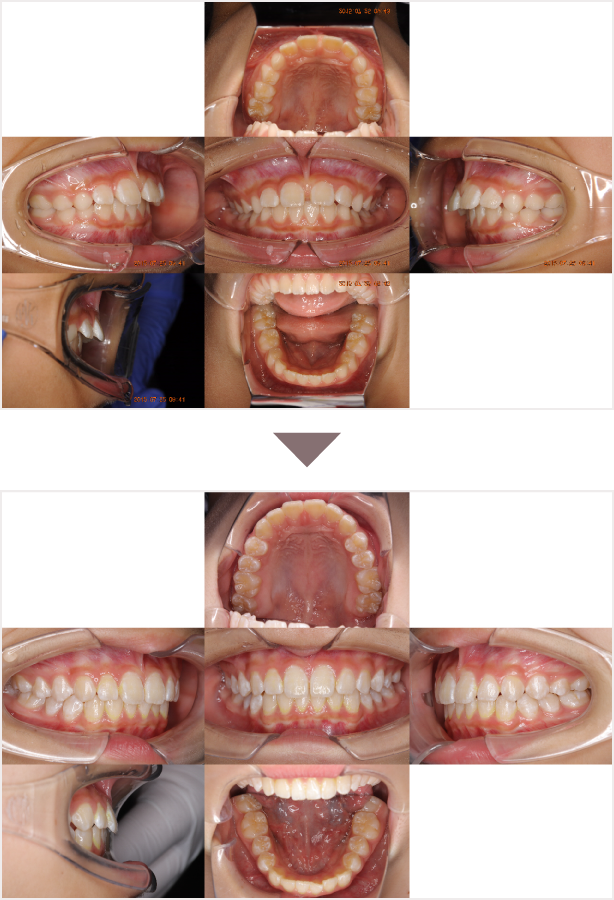

症例叢生

性別

期間7年7ヶ月

治療内容N-Bimler装置、Neo-Capを使用して治療

治療における

副作用・リスク

装着しないと効果は出ません

金額ビムラー装置:550,000円

ネオキャップ:4本

合計:572,000円